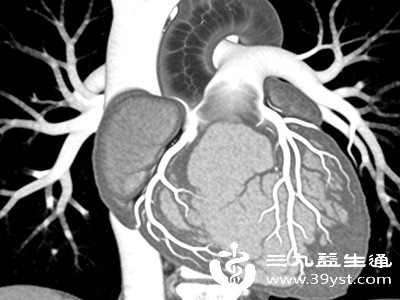

四、心脏CT血管造影(CTA):血管的“高清扫描仪”

心脏CTA主要用于检查心脏的血管状况。检查前,患者需要通过静脉注射造影剂,使冠状动脉在CT扫描下显影,随后CT设备对心脏进行多角度、高分辨率的扫描,生成冠状动脉的清晰图像。通过这些图像,医生可以观察冠状动脉是否存在狭窄、堵塞、钙化等病变,以及病变的位置、程度和范围。

冠状动脉是为心脏供血的重要血管,一旦出现狭窄或堵塞,就可能导致心肌缺血,引发心绞痛、心肌梗死等严重后果。心脏CTA能精准定位血管病变,对于评估冠心病的风险和制定治疗方案具有重要意义,堪称心脏血管的“高清扫描仪”。